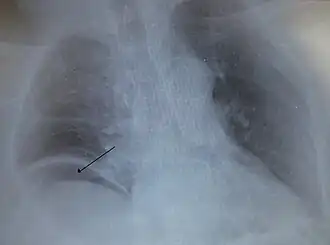

Aire libre bajo el diafragma derecho desde un intestino perforado. | ||